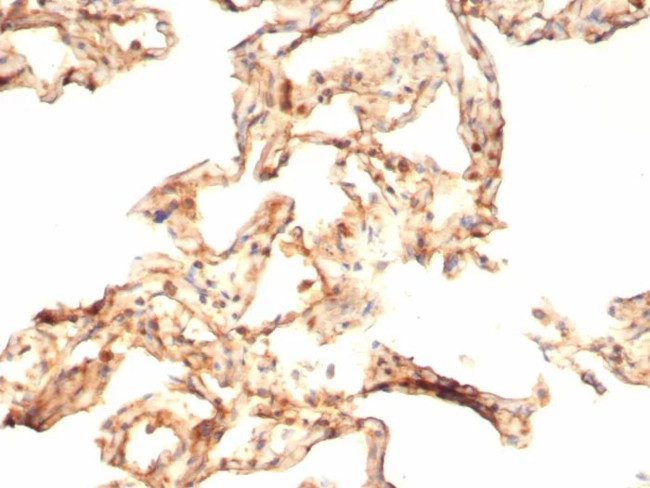

IL-6 (Interleukin-6)/Interferon beta-2 (Hybridoma Growth Factor) Antibody in Immunohistochemistry (Paraffin) (IHC (P))

Formalin-fixed, paraffin-embedded human COVID positive lung stained with IL-6 Mouse Monoclonal Antibody (IL6/4643) at 2 µg/mL. HIER: Tris/EDTA, pH9.0, 45 min. 2°C: HRP-polymer, 30 min. DAB, 5 min. {{ $ctrl.currentElement.advancedVerification.fullName }} 验证信息 View more